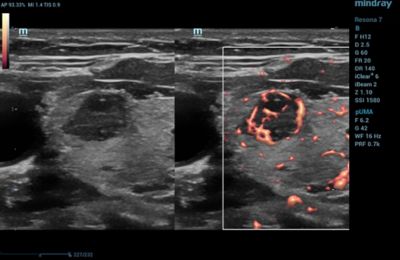

Thyroid

CDI is routinely used in thyroid gland imaging to further classify and aid in diagnosing thyroid lesions.

Power Doppler Imaging of Thyroid Lesion

Power Doppler ultrasound is more sensitive than CDI, which makes it an excellent option for alternative assessment methods. It is commonly used to examine organs or structures with small vessels, such as in thyroid, breast, testicular, and musculoskeletal applications. It may also be used to evaluate tumor perfusion, as well as subtle ischemic areas.